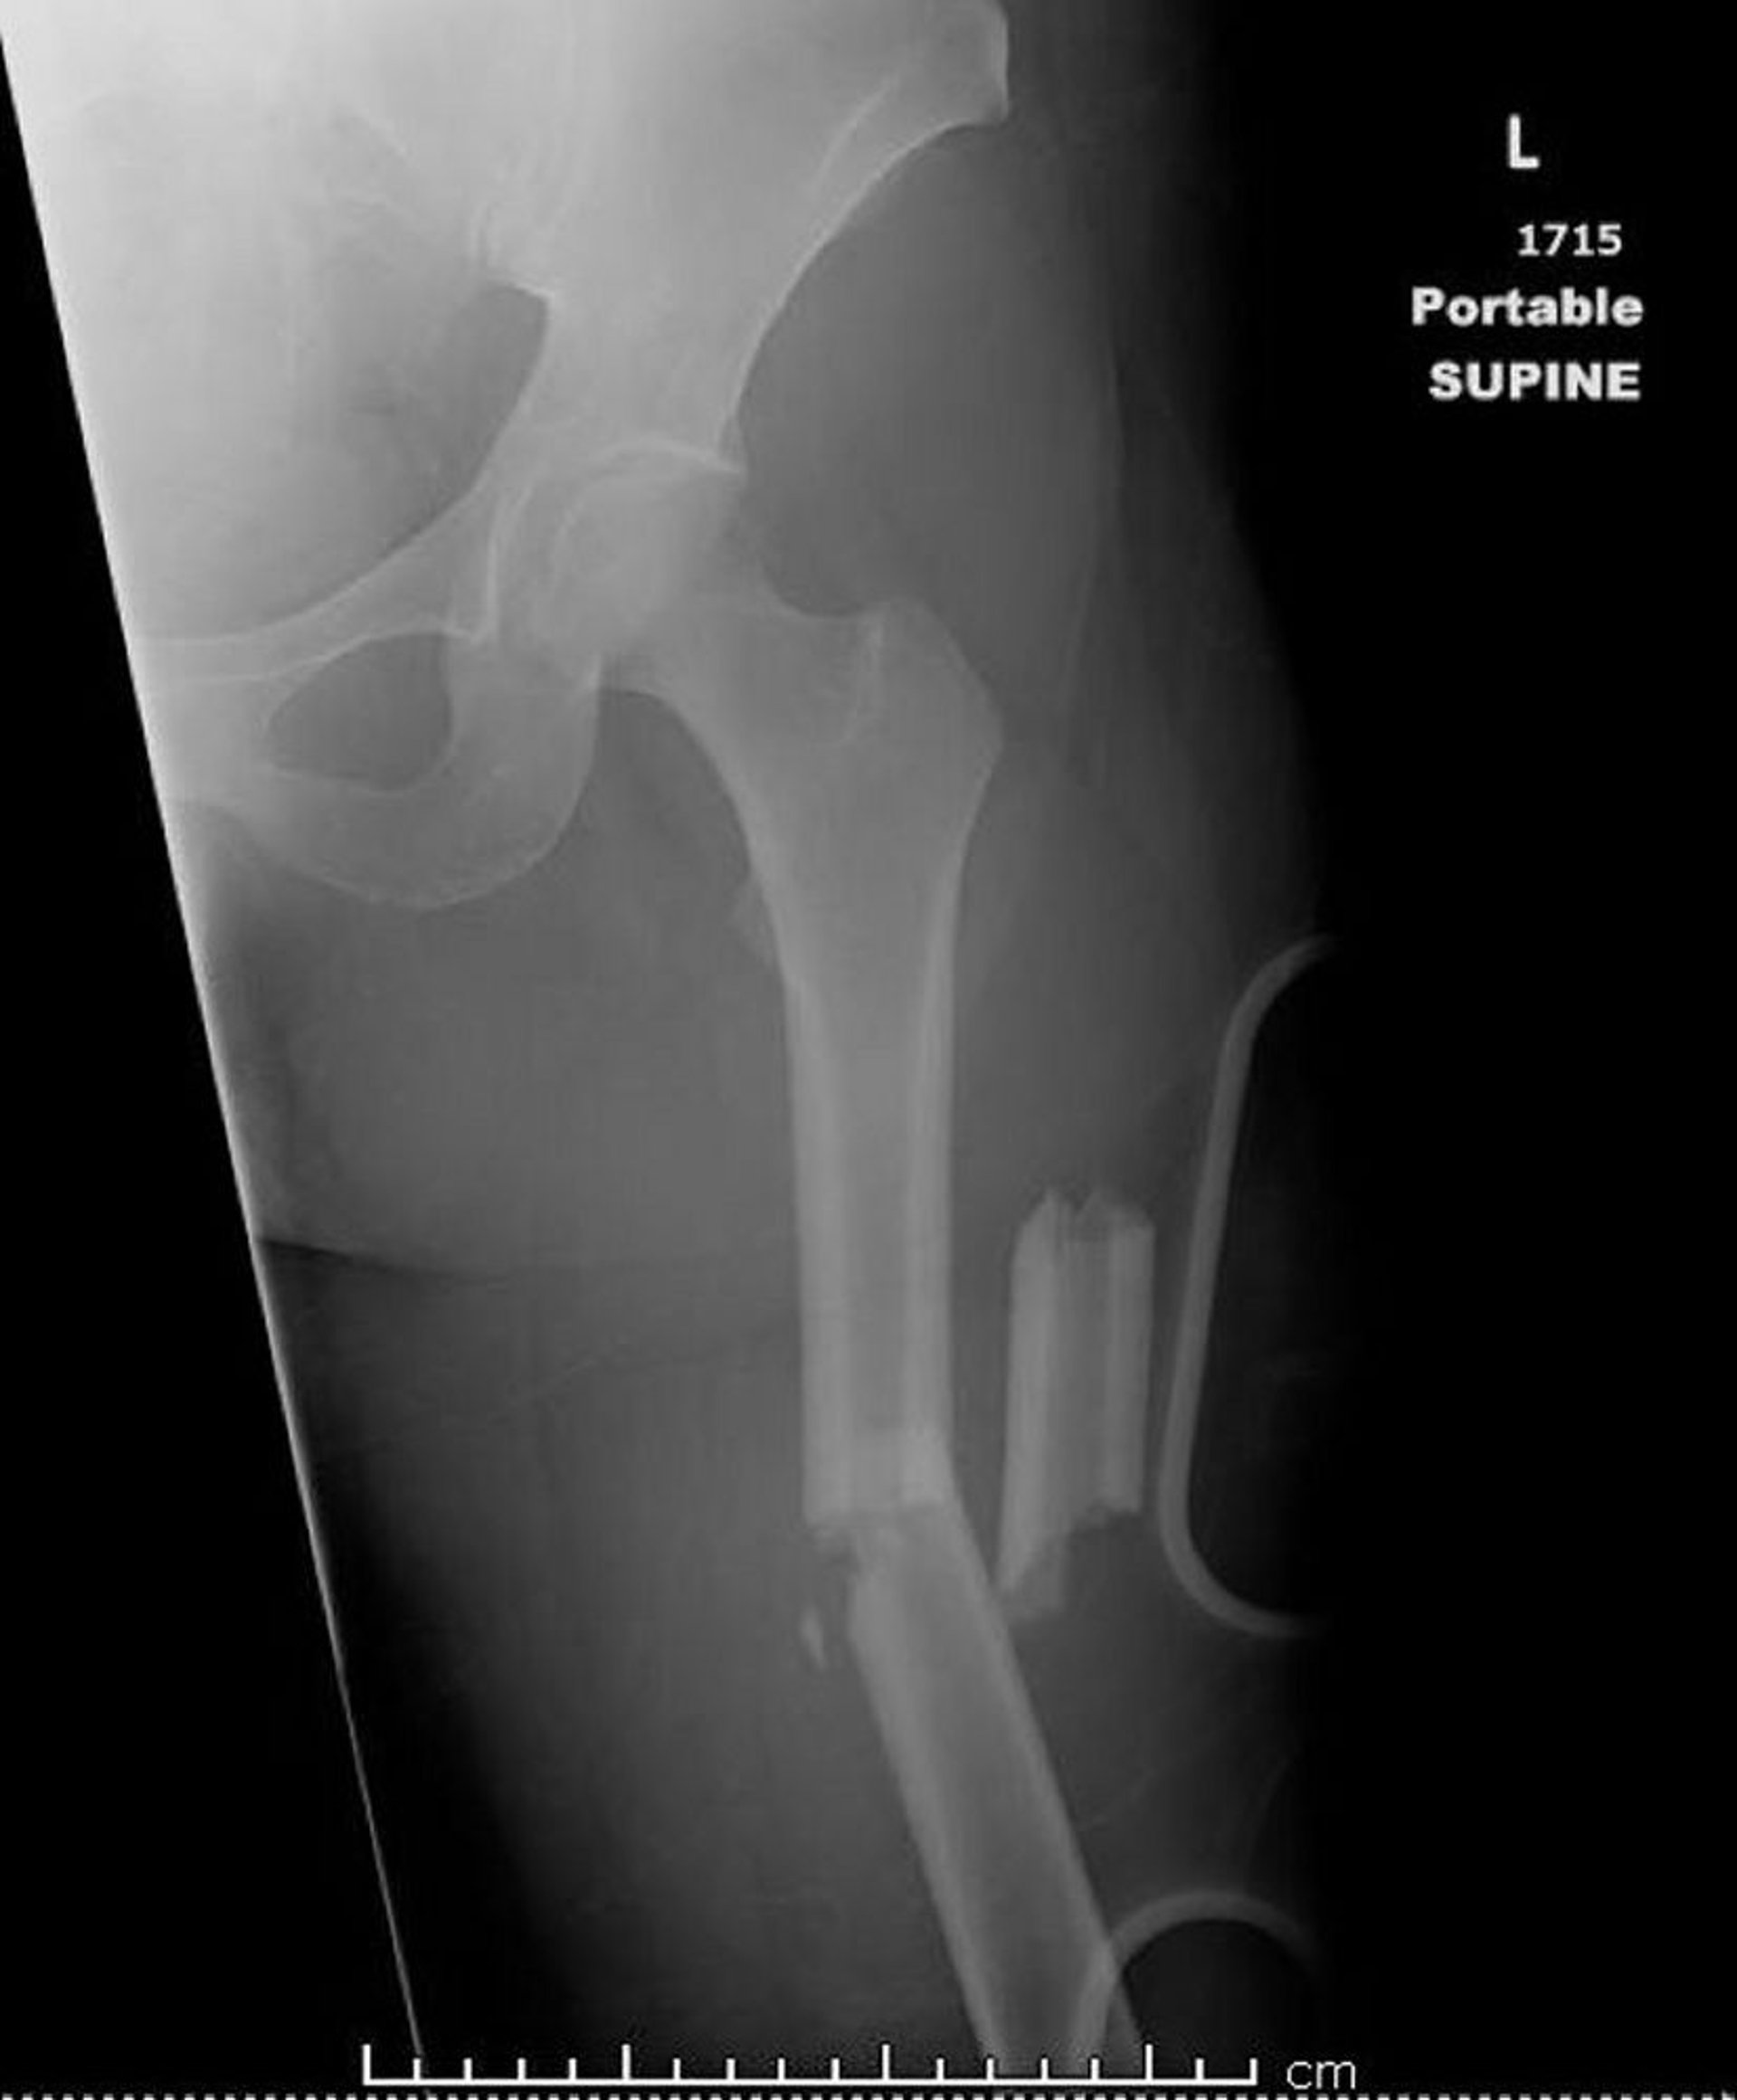

Fractura del fémur del conducto medio (1)

Esta imagen muestra una fractura conminuta angulada del tercio medio de la diáfisis femoral, que está acortada.

Image courtesy of Danielle Campagne, MD.